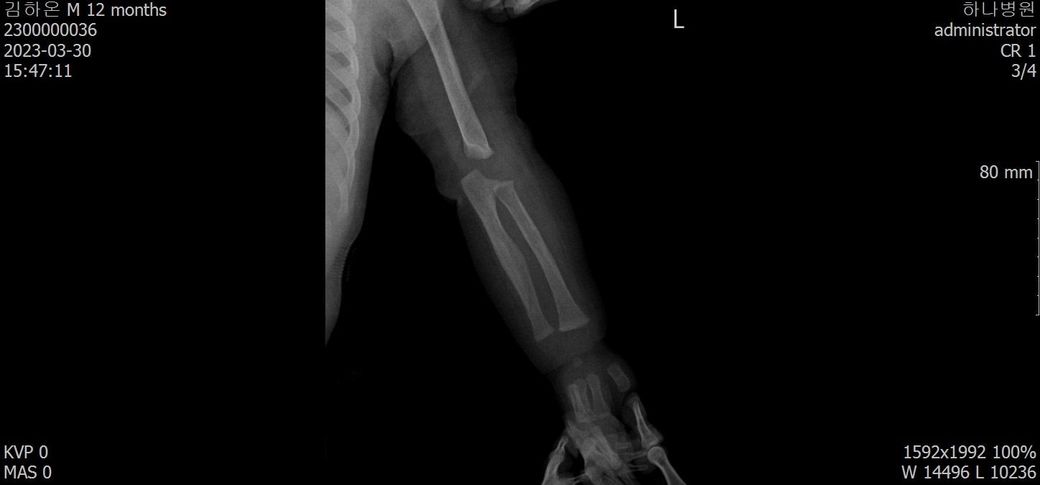

다름이 아니라, 첨부드린 엑스레이(X-ray) 사진처럼 골절 사실을 알게 되고 골절 발생 시점 대략적으로나마 추정시기를 파악하려고 문의 드리게 되었습니다

1) 3월 30일 촬영한 X-ray만으로 정확한 골절 시기를 100% 특정하는 데에는 한계가 있다는 점 충분히 인지하고 있기에 촬영날짜 기준으로 대략적으로 어느정도 시점에서 발생되었을 것으로 추측(ex 당일, 7~10일전, 7~14일 전, 10일 ~ 20일전, 14일 ~ 30일전 등등등)되는지 이해하고 싶습니다.

• 3번 째 사진

엑스레이상 골절선이 뚜렷한 시기는 1주, 골막 반응이 보여진다면 1~2주, 연골성 가골이 형성되는 시점은 2~3주, 가골이 명확해지면 3~6주 정도로 추정할 수 있습니다.

다만 "3월 30일 영상에서 골절선이 비교적 뚜렷하고, 4월 10일에 상당한 가골(callus)이 형성"된 점을 종합하면 "골절은 3/30 당일보다는 최소 수일~2주 이상 이전에 발생했을 가능성이 높습니다."

올려주신 사진을 참고하였을 때 3월말에는 켈로스(가골)형성이, 4월에는 유합이 진행되고 있는 상태를 고려해볼 수 있겠습니다.

회복 경과를 바탕으로 대략적인 시점을 고려하여 보자면 3월 말 시점에서 약15-20일 정도의 기간을 골절 발생시기로 의심해볼 수 있겠지만, 정확한 소견은 관련 전문의의 의견을 들어보심이 좋습니다.